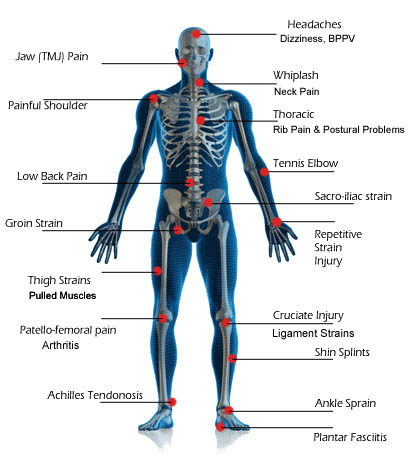

The treatment prevents muscle atrophy which can lead to stress incontinence, vaginal laxity (relaxation), vaginal dryness, itching and burning, diminished sexual sensation and dyspareunia.

- In addition to narrowing and remodeling of the vagina, the treatment simultaneously corrects statics and dynamics of pelvic connective tissue and aids in treating and resolving stress incontinence

- Aids in treatment of painful and uncomfortable intercourse

In recent years HIFU technology has been successfully applied in treatments of vaginal relaxation (VRS) and stress incontinence (SUI). Precise application of HIFU waves to vaginal walls at a depth of 3 to 4.5mm warms submucosa and mucous membrane to 65⁰C. This method practically instigates connective tissue of mucous membrane to regenerate. The treatment results in higher numbers of stronger, remodeled and narrowed collagen fibers which permeate and provide strength of vaginal walls. In addition, biostimulative effects of HIFU wave initiated regenerative processes have positive impacts on the elastic fibers of mucosa and pelvic muscles. Final results of the treatment are reflected by a narrowed vaginal canal with stronger, more resistant and healthier walls. All these effects are beneficial in the treatment of SUI hence why HIFU is also applied in treatments of first and second degree SUI whilst third degree SUI requires surgery. HIFU application in treatment of first and second degree SUI can significantly delay the development of third degree SUI and therefore delay or completely eliminate the need for surgical treatment.

We highly recommend this method for resolving vaginal relaxation, stress urine incontinence, painful, uncomfortable and diminished sensations of sexual intercourse. It’s a very simple method of improving the complete enjoyment and satisfaction of both partners.